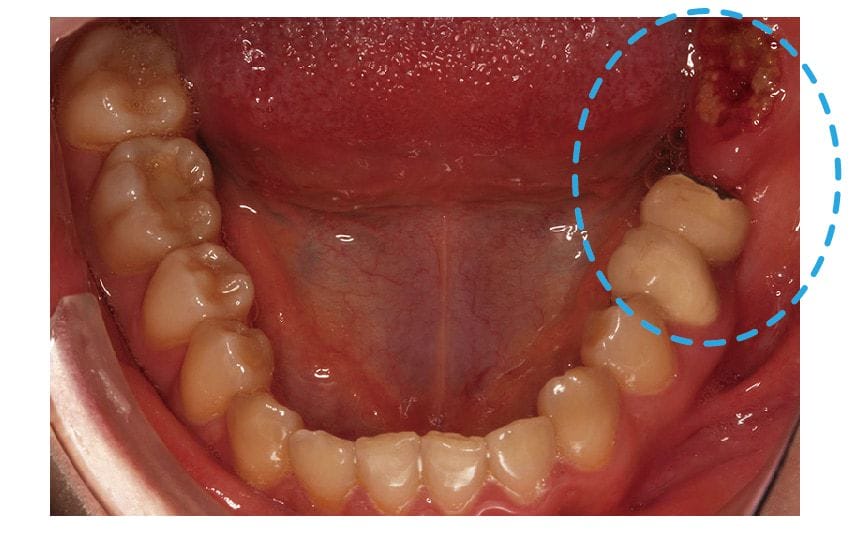

圖示:左下後牙區的假牙和臼齒殘根 圖示:左下後牙區X光片,箭頭處為假牙與臼齒殘根

這可能是因爲是她早期左下的臼齒缺牙,當時在其他診所是用傳統牙橋修復。

傳統牙橋的缺點除了是前後牙齒需要犧牲齒質磨小才能印模製作以外,牙橋底下也會產生清潔死角,導致難做到良好的清潔,很容易發生再蛀牙或是牙周疾病等後遺症,久而久之後面的牙齒蛀斷了成為殘根。

Miss Sung 在牙周方面,雖然本身沒有什麼主觀的症狀,但還是有部分區域有比較深的牙周囊袋,與初期的齒槽骨流失。特別在左上後牙區也是有一組密合度已經不甚理想的假牙,容易造成牙菌斑或牙結石的殘留,屬於牙周病風險比較高的區域。

圖示:主訴患處和左上牙橋,都有牙齦發炎紅腫的狀況